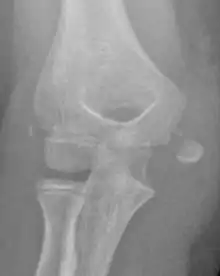

The diagnosis is confirmed with X-rays and occasionally with a CT scan.

In all injuries to the medial epicondyle, radiographs (x-rays) are imperative. Computed tomography scans are occasionally useful in evaluating the degree of fracture displacement or the involvement of the joint surface.

Studies generally use the x-ray appearance of the arm to determine how displaced a fracture is. The definition of ‘displaced fractures' are variable, with anything from 2mm to more than 15mm;[4] however x-rays on which this assessment is made are known to be hugely misleading with fractures showing little displacement having >10mm displacement using CT scans.[5][6] The practical approach is therefore to assume that any fracture that has any degree of displacement on x-rays is ‘displaced’.